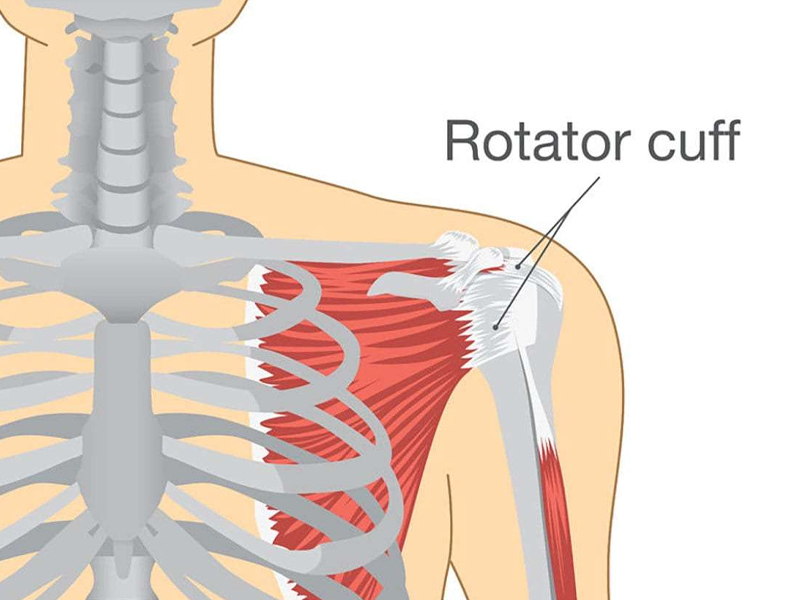

Shoulder arthroscopy (bankart repair, laterjet,frozen shoulder, rotator cuff

repair)

Rotator Cuff

A rotator cuff tear is a common cause of shoulder pain and disability among adults. Each year, almost ...